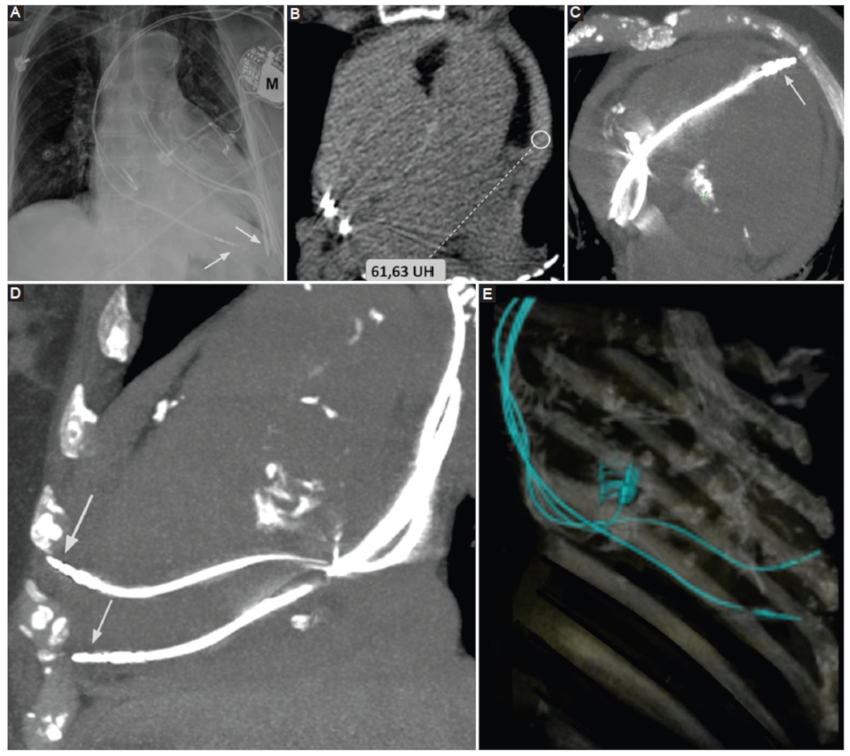

Iatrogénico: en este grupo se engloban el hemopericardio secundario a procedimientos cardiacos invasivos tales como la intervención coronaria percutánea o la colocación de marcapasos (Fig. 9); o como consecuencia de una cirugía cardiovascular (Fig. 10).

Pericarditis constrictiva

Representa una condición clínica resultante de una menor distensibilidad del pericardio2,14. Si bien su etiología es multifactorial, se asocia con mayor frecuencia al antecedente de pericarditis autoinmune, neoplasias del pericárdico y pericarditis bacteriana6,15.

Los síntomas clásicos de presentación son secundarios a falla diastólica, con signos de insuficiencia cardiaca derecha en ausencia de patología cardiaca subyacente6.

La TCMC presenta gran rédito para la identificación de la pericarditis constrictiva, así como también para discriminar los hallazgos de su principal diagnóstico diferencial que es la miocardiopatía constrictiva (Fig. 12). Cabe remarcar que si bien ambas entidades presentan similar escenario clínico, la pericarditis constrictiva es potencialmente tratable, a diferencia de la miocardiopatía constrictiva, que se asocia con un pronóstico desfavorable6.

Entre los hallazgos clásicos visualizados por TCMC se mencionan:

Engrosamiento pericárdico mayor a 4 mm. Este hallazgo resulta poco sensible, ya que puede presentarse con pericardio de grosor conservado16.

Calcificación de las hojas pericárdicas16.

Signos indirectos como reducción de volumen del ventrículo derecho de morfología tubular16.

Cabe mencionar que el engrosamiento y la presencia de calcificaciones resultan datos muy sugestivos de esta entidad, pero con limitada sensibilidad. En este sentido, Talreja et al. (16, en su serie de 143 pacientes con diagnóstico definitivo de pericarditis constrictiva, encontraron que un 18% de los casos se presentó con grosor pericárdico normal, y entre un 30-40% de los casos se presentó con calcificaciones pericárdicas.

La TCMC permite además una correcta evaluación prequirúrgica, considerando la pericardiectomía como tratamiento de elección2.